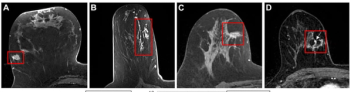

An artificial intelligence algorithm for dynamic contrast-enhanced breast MRI offered a 93.9 percent AUC for breast cancer detection, and a 92.3 percent sensitivity in BI-RADS 3 cases, according to new research presented at the Society for Breast Imaging (SBI) conference.

An emerging nomogram model for intra-tumoral heterogeneity quantification with breast MRI demonstrated an average 85 percent sensitivity in external validation testing for predicting pathologic complete response to neoadjuvant chemotherapy for breast cancer.

New multicenter research suggests that radiomic features derived from breast MRI may enhance prognostic capabilities with disease upstaging for ductal carcinoma in situ (DCIS).